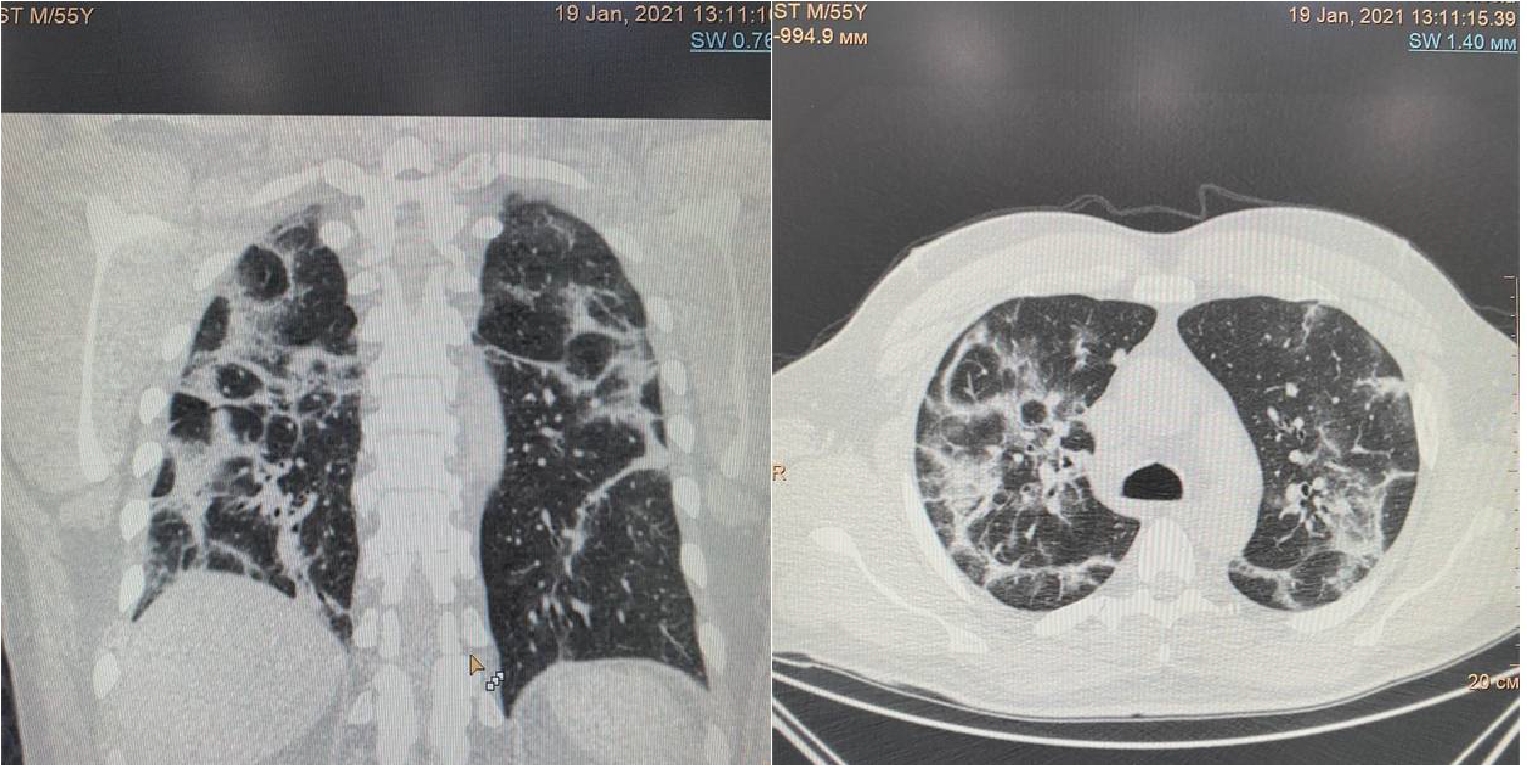

Проведено дренирование плевральной полости справа по Бюлау. В результате отмечена отчетливая положительная динамика в виде устранения одышки, повышения SpO2. Через 3-е суток при контрольной рентгенографии органов грудной клетки выявлен верхушечный пневмоторакс справа (рис. 6), проведена пункция плевральной полости, дренирование продолжено. На фоне устойчивой положительной динамики в дальнейшем, на 23-е сутки терапии пациент выписан в удовлетворительном состоянии.

Рисунок 6. Рентгенограмма органов грудной клетки – признаки двусторонней полисегментарной интерстициальной пневмонии (объем поражения 30%, КТ-2). Верхушечный правосторонний пневмоторакс